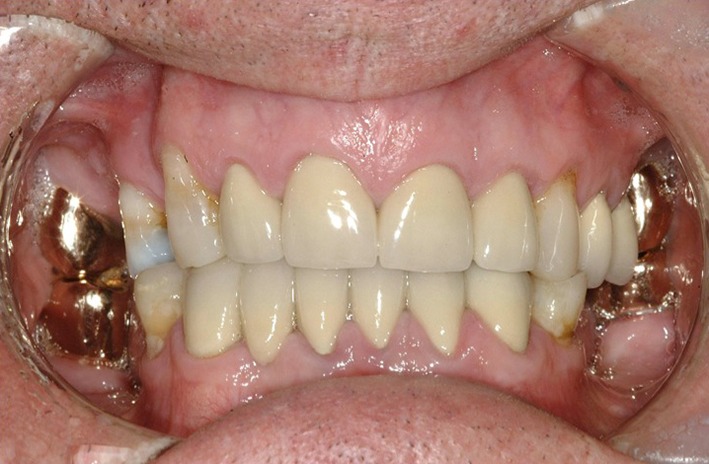

Fig. 13.

a Post-operative buccal view. b Post-operative maxillary occlusal view. c Post-operative mandibular occlusal view